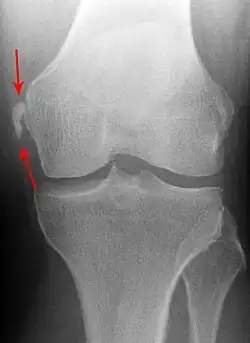

Pellegrini-Stieda syndrome. Also visible is a fracture of the patella. |

Pellegrini–Stieda syndrome (also called Stieda disease and Köhler–Pellegrini–Stieda disease) is the ossification of the superior part of the medial collateral ligament of the knee. It is a common incidental finding on knee radiographs. It is named for the Italian surgeon A. Pellegrini (b. 1877) and the German surgeon A. Stieda (1869–1945).[1] While the eponym refers to Pellegrini and Stieda, the condition was first discovered by Köhler in 1903, before any namesakes. Pellegrini-Stieda combines the aforementioned radiographic findings and concomitant medial knee joint pain or restricted range of motion.[2]

Diagnosis is typically made on radiographs demonstrating the Pellegrini-Stieda syndrome sign accompanied by pain or restriction of range-of-motion of the knee joint.[2] Pellegrini-Stieda syndrome sign is typically described by a longitudinally linear opacity, which is a process that is describes characteristic of calcification in the soft tissue located medial to the medial femoral condyle.[2] This calcification seen on imaging represents the ossification of the medial collateral ligament, which typically does not develop until approximately three weeks after the initial injury.[2]It is important to note to distinguish this radiographic finding from that of a medial femoral condyle avulsion fracture, which is an injury in which a pulling force of a tendon or ligament fractures away a piece of the bone from its attachment site.[2]